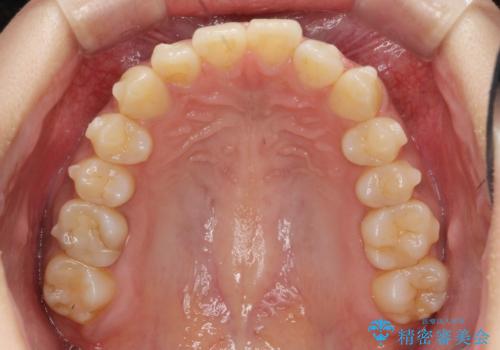

前歯のがたつきをすっきり マウスピース矯正

- 長年気になっていた前歯のがたつきをマウスピース矯正で治したい!と希望され来院されました。

奥歯の噛み合わせには問題がなく、前歯のがたつきの改善のみで十分に審美的な結果が得られるため、ワイヤーではなくマウスピース矯正での治療を計画します。

しっかりと前歯のがたつきは改善し見た目が大きく良くすることができました。